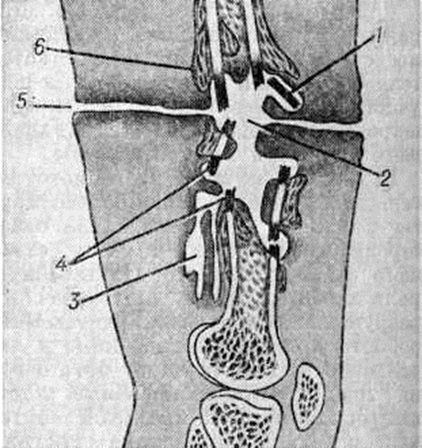

В ходе нагноения в окружающих очаг тканях развёртываются пролиферативные и дистрофические процессы. В результате пролиферации тканей возникает гноеродная оболочка, а затем формируется костная мозоль (смотри полный свод знаний) с последующей консолидацией перелома или образуются лишь костные разрастания по краям отломков (рисунок 4). Возникшая костная мозоль включает в себя гнойники с секвестрами (цветной рисунок 2) и играет т. о. роль секвестральной капсулы, из которой свищевые ходы ведут на поверхность кожи (рисунок 5). Дистрофические изменения выражаются в диффузной рарефикации, а позже в очаговой эбурнеации кости (смотри полный свод знаний) в зоне образования мозоли. В окружающих мягких тканях и в соседних суставах развиваются явления атрофии.

Различают ранние и поздние гнойно-воспалительные осложнения огнестрельных переломов костей. Ранние осложнения, возникающие непосредственно после ранения, в большинстве случаев связаны с гнилостным распадом костного мозга или гнойным воспалением его внутри костномозгового канала и характеризуются бурным клинические, течением с выраженными общими реакциями, как и при гематогенном Остеомиелит Поздние осложнения (спустя 1—2 месяцев после ранения) развиваются обычно вне костномозгового канала, главным образом в элементах опорной костной ткани; при этом наблюдается выраженное отграничение процесса и образование гнойной полости вокруг мёртвых костных осколков и инородных тел (рисунок 8). Репаративно-ре генеративные процессы, приводящие к патологический изменениям в виде гиперостоза (смотри полный свод знаний) и склероза плотной костной ткани (смотри полный свод знаний Остеосклероз), составляют сущность этого вида осложнений и обусловливают переход ранних его форм в хронические.